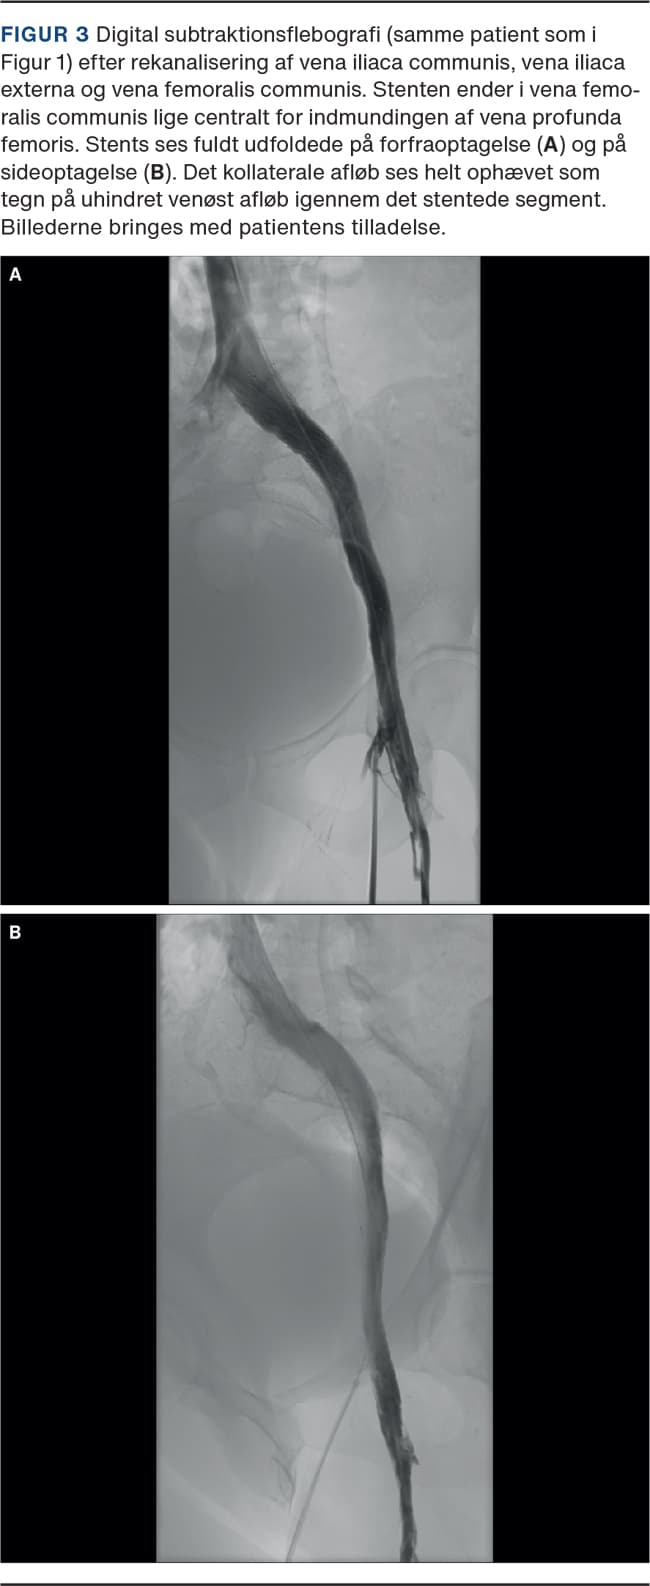

Endovaskulær behandling, dvs. ballondilatation og stentning, udføres for at genetablere det centrale venøse afløb fra ekstremiteten. Indsættelse af en stent forudgås af prædilatation af det obstruerede venesegment med højtryksballon og efterfølges af efterdilatation af selve stenten, ligeledes med højtryksballon (Figur 2 og Figur 3). Dilatationen er smertefuld, og indgrebet foretages derfor ofte i generel anæstesi.